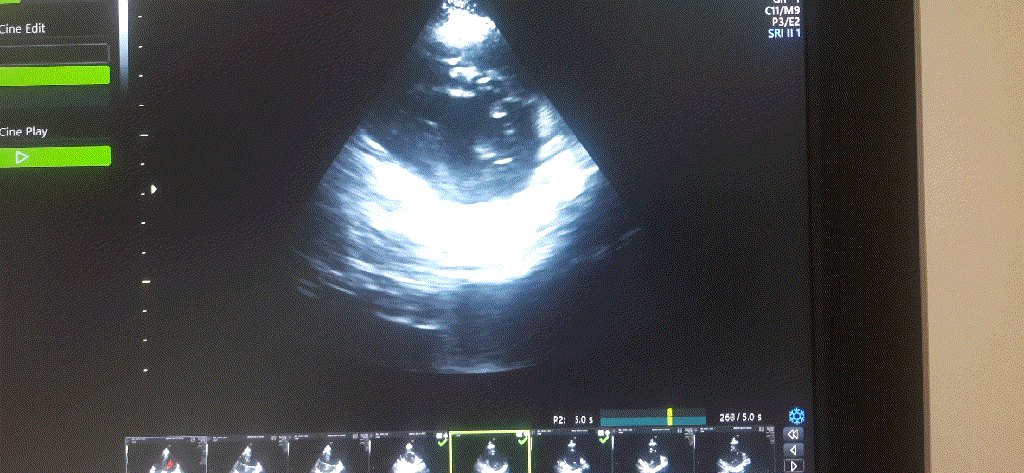

This is a 27-year-old woman who was referred for routine* cardiac evaluation. What do you see?

What is the diagnosis?

This echo clip is from a woman who is 8 months pregnant. What you are seeing is perfectly physiologically and normal. On lying down there is a mechanical push of the diaphragm altering the LV shape and contraction. In the short axis, the left ventricle is contracting well, but the shape is not spherical in systole implying some desynchrony. Further, the IVS arena is contracting vigorously, which makes, the other segments appear to be poorly contracting. (Someone could report it as a wall motion defect in antero- lateral segments inviting temporary panic)